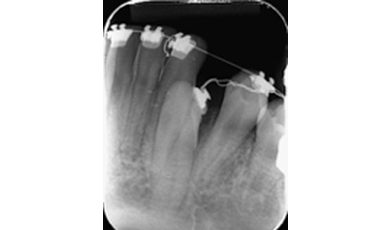

Canino inferior esquerdo incluso (dente 33)

As imagens abaixo retratam um caso clínico em que a paciente compareceu ao consultório para avaliação ortodôntica e por meio da imagem radiográfica (panorâmica) foi possível identificar que o canino inferior esquerdo (dente 33) encontrava-se incluso, sendo necessária a intervenção ortodôntica para o seu tracionamento.